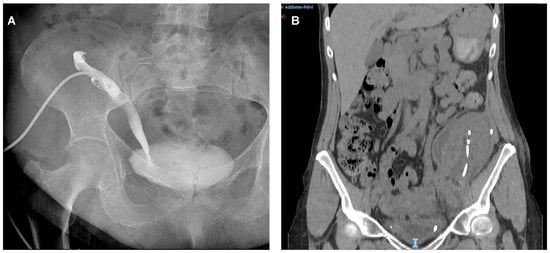

| Urological Complications: | 32 (7%) |

| ● Ureteral Stenosis | 20 (62.5%) |

| ● Urinary Fistula | 7 (21.9%) |

| ● Urinary Retention | 5 (15.6%) |

| Time urological complication onset: | |

| ● Early (≤3 months) | 21 (65.6%) |

| ● Late (>3 months) | 11 (34.4%) |

| Type of UC treatment: | |

| ● Nephrostomy + ureteral stenting | 17 (53.1%) |

| ● Cystoscopy + ureteral stenting | 3 (9.4%) |

| ● Nephrostomy | 2 (6.2%) |

| ● Foley catheter insertion | 5 (15.6%) |

| ● Surgical intervention | 5 (15.6%) |